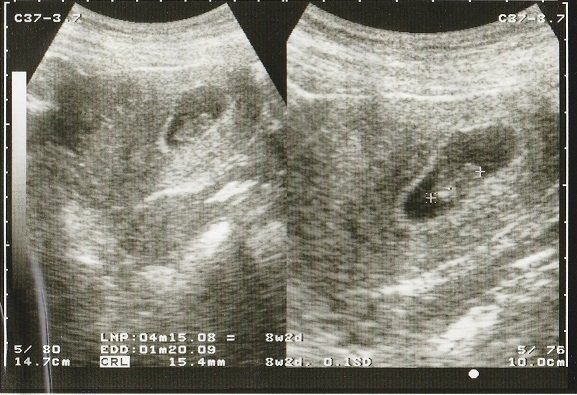

水野谷つむぎさんの妊娠8週のエコー写真 少しずつ大きくなっている赤ちゃん

赤ちゃんの大きさは1.5㎝くらい。この頃、つわりらしきものを感じ始めました。食の好みが変わることはありませんでしたが、量が食べられなくなり、とても疲れやすく、帰宅後ご飯を食べたら力尽き、午前3時ごろにやっと起きて、洗い物をするような日々でした。

そんな頃に病院から突然の電話があり、なんと病院が閉院することを聞かされました。そして、「もう妊娠3カ月に入るので、急いで別に出産する病院を探して下さい」と言われました。妊娠3カ月になったら入院予約、前金入金の病院が多いための指示でした。あまりのことに、電話を切った後、呆然と立ち尽くしましてしまいました。